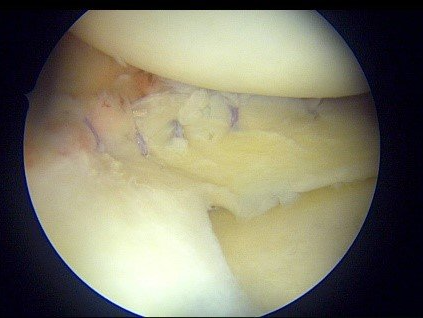

- Réparation méniscale sous arthroscopie : la suture méniscale est proposée chez des patients plutôt jeunes, actifs ou sportifs lorsque la fissure est située en zone favorable (rouge-rouge ou rouge blanc). La suture méniscale est un moyen de prévention de la survenue d’arthrose. En réparant le ménisque, celui-ci va reprendre son rôle d’amortisseur antichoc et de guide du genou. Toutefois, il faut soigneusement sélectionner les patients candidats, car les suites postopératoires sont plus contraignantes. D'abord, marche en appui « soulagé » à l’aide de béquilles pendant 3 semaines. La marche en plein appui sera reprise par la suite. La reprise du sport est attendue au 3e mois postopératoire.

- Méniscectomie partielle sous arthroscopie : lorsque le ménisque est douloureux, mais que la suture n’est pas envisageable, chez des patients peu demandeurs sur le plan sportif ou plus âgés, on proposera une chirurgie d’ablation partielle la plus économe possible de la zone malade du ménisque. Cette technique a l’avantage de permettre un retour rapide aux activités (marche en plein appui dès la sortie de la clinique le jour même) et une reprise du travail accélérée. Toutefois, le risque d’arthrose est majoré. Il faut cependant nuancer un point. Ce n’est pas la méniscectomie qui aggrave le risque d’arthrose, mais le fait que le ménisque lésé ne remplit plus son rôle d’amortisseur. La méniscectomie économe doit être effectuée par un chirurgien entraîné pour ne pas être excessive.

Une autre incision « instrumentale » de 5 à 10 mm permettra le passage des instruments de chirurgie. Grâce à l’arthroscopie, on peut désormais effectuer de nombreuses opérations sans laisser de disgracieuse cicatrice sur le genou.